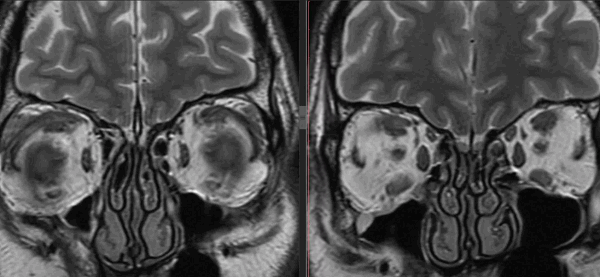

Тот же пациент, исследование в динамике через 4,5 года

Исследование в 2008 году Исследование в 2013 году